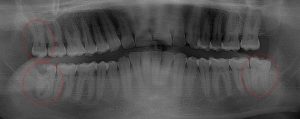

This 34 year old patient has all four third molars present (circled) and fully erupted into occlusion. They appear disease free…but are difficult to keep clean. 3rd molars are the most likely teeth to decay or have gum disease with a >98% probability that decay and gum disease will occur around all four teeth over this patient’s life time.